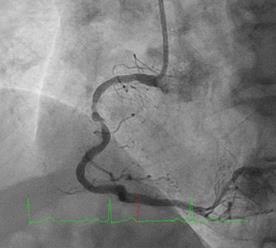

Can thiệp ngã ba động mạch liên thất trước và nhánh chéo 1 với hai stent có bọc thuốc bằng kĩ thuật cullote. Tiếp tục can thiệp động mạch vành phải với ống thông can thiệp (guiding catheter) (Cordis JR4 cm 6Fr) và dây dẫn (Asahi Sion 0.014”). Nong tổn thương bằng bóng 3.5 x 15mm (Neich Sapphire), bóng 4.0 x 12 (NC Quantum Apex), bóng cắt 3.5 x 15 (Cutting balloon, Angiosculpt) không làm vỡ được mảng vữa xơ. Quyết định dùng hệ thống khoan cắt mảng vữa xơ với dây dẫn mềm (Boston Scientific Rotablator Rotalink Plus) và mũi khoan (burr) 1.5mm. Tuy nhiên vì kích thước động mạch quá lớn nên mũi khoan đi qua tổn thương mà không chạm vào mảng vữa xơ được. Chuyển sang mũi khoan có đường kính lớn hơn 2.15mm với tốc độ khoan 150000 vòng /phút. Khi mũi khoa đi qua được 1/3 tổn thương thì không thể di chuyển được tiếp. Nhận định tại thời điểm đó là mũi khoan bị kẹt trong tổn thương tại đoạn giữa của động mạch vành phải. Ngay lập tức các bác sỹ có kinh  nghiệm can thiệp trong bệnh viện được mời đến phòng can thiệp đồng thời thông báo cho các phẫu thuật viên tim mạch chuẩn bị trong trường hợp cần thiết. Bệnh nhân có biểu hiện đau tức ngực trái, tuy nhiên mạch và huyết áp tương đối ổn định, điện tim không thay đổi. Dòng chảy trong động mạch vành còn duy trì nhưng chậm TIMI 2. Sau khi hội ý, hướng xử trí đầu tiên là dùng dây dẫn cứng Conquest Pro (Asahi) để đi qua tổn thương nhưng không thành công. Sau đó chúng tôi quyết định cắt đoạn đầu của hệ thống nối mũi khoan, đưa ống thông heartrail (Terumo) sát vào mũi khoan nhằm thay đổi tư thế và cố định mũi khoan vào dây dẫn để đưa ra ngoài. Cuối cùng mũi khoan được đưa ra ngoài thành công. Tổn thương tiếp tục được nong bằng bóng cắt và bóng áp lực cao và đặt được giá đỡ kim loại (stent) bọc thuốc 4.0 x 26mm. Kết quả là động mạch vành được mở rộng hoàn toàn, bệnh nhân không còn đau ngực, huyết động ổn định.

Hình 1: A- hình ảnh động mạch vành trước can thiệp; B - dùng bóng cắt (cutting balloon) không phá vỡ được cấu trúc mảng vữa xơ; C – mũi khoan 1.5 không chạm vào được mảng vữa xơ vôi hóa; D – mũi khoan 2.15 bị tắc tại vị trí hẹp.

Hình 2: A- đường dẫn của mũi khoan được cắt bằng kéo; B – đưa ống thông Heartrail vào sát mũi khoan; C – toàn bộ hệ thống được đồng thời đưa ra ngoài; D – hình ảnh sau đặt stent.